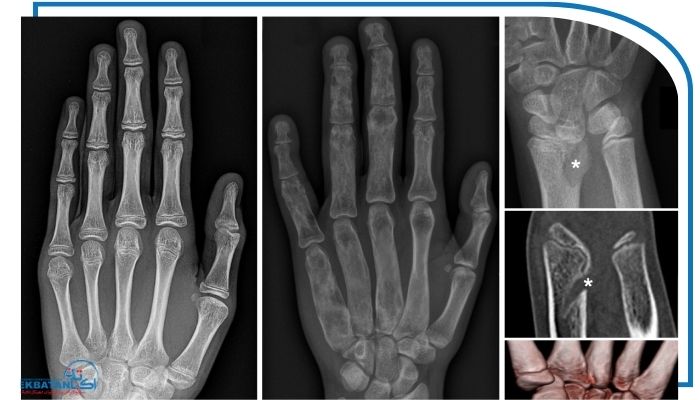

تصویربرداری

تصویربرداری بخش اصلی در تشخیص اختلالات استخوانی محسوب می‌شود. رادیوگرافی ساده (X-ray) دقیق‌ترین روش برای ارزیابی صفحات رشد، تراکم استخوانی و وجود تغییر شکل‌هاست. در کودکان با انحراف پا یا ناهنجاری اندام تحتانی، تصویربرداری خاصی به نام تری‌جوینت (Hip–Knee–Ankle view) انجام می‌شود که محور مکانیکی اندام‌ها را از لگن تا مچ پا نشان می‌دهد و در تصمیم‌گیری درمانی بسیار اهمیت دارد. MRI برای بررسی جزئیات غضروف‌ها، صفحات رشد و بافت نرم اطراف استخوان به‌کار می‌رود و در تشخیص آسیب‌های اولیه یا مادرزادی مفید است. سی‌تی اسکن (CT Scan) جزئیات ساختاری استخوان را با دقت بالا نمایش می‌دهد و معمولاً در موارد پیچیده یا پیش از جراحی استفاده می‌شود. در صورت شک به کاهش تراکم استخوان، از DXA Scan برای سنجش تراکم استخوان و تشخیص پوکی استخوان دوران کودکی استفاده می‌شود.